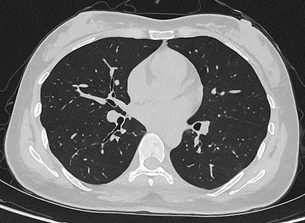

联影uCT Ultima扫描的0.2mm肺部超高清成像,扫描剂量低至0.1mSv

目前,华西厦门医院已基于该设备完成第一批患者扫描。华西厦门医院党委书记廖志林表示,光子计数能谱CT的临床落地实现了对国外“卡脖子”技术的突破,大幅降低了辐射剂量,让患者CT扫描更安全。临床案例显示,设备在低剂量条件下仍可实现肺结节的高清成像,临床价值突出。该设备将在医院的全链条、全生命周期健康管理服务中发挥重要作用。